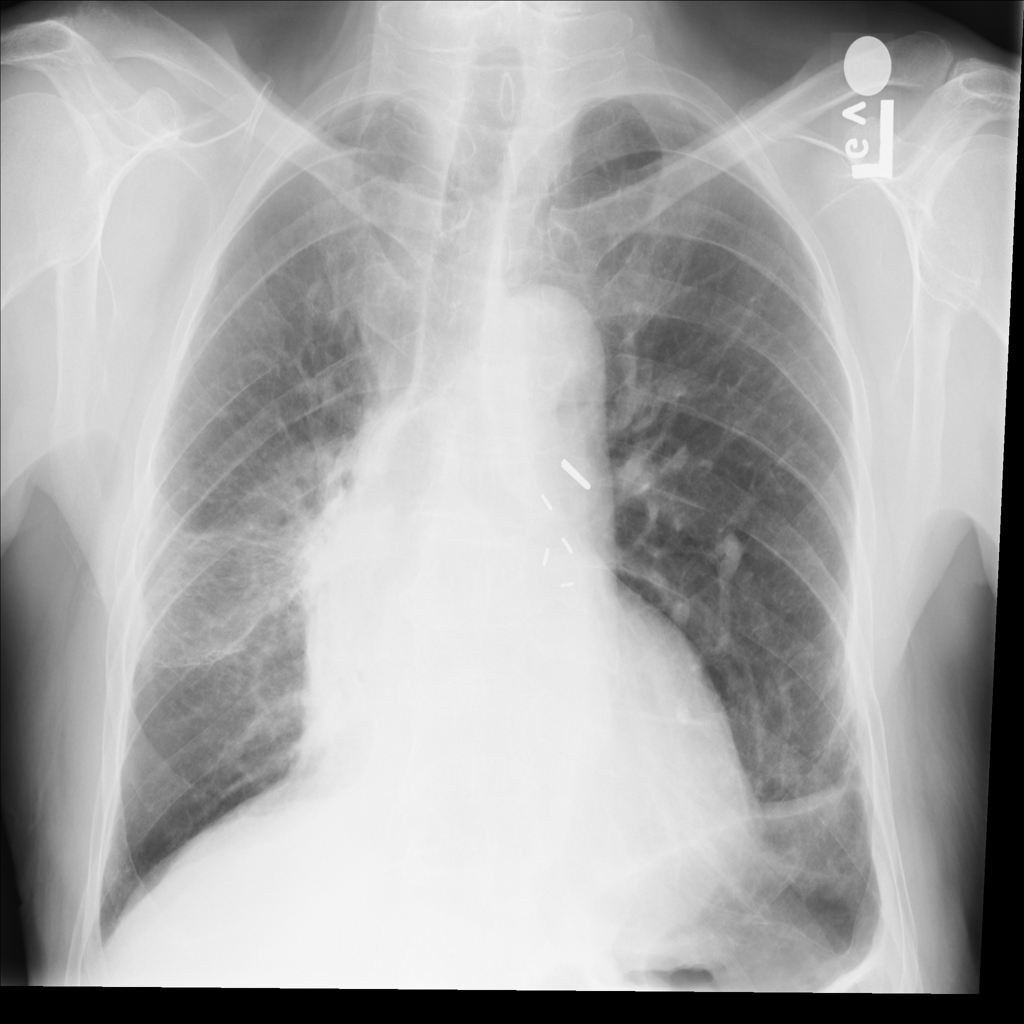

PAT-EBE1 · IMG-019Pneumonia

PAT-EBE1 · IMG-019

AP